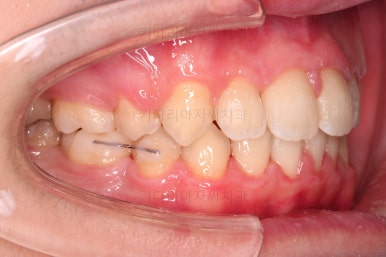

전후 비교입니다.

입은 약간만 들어가게끔 했고요.

웃을 때의 입매가 참 좋아졌네요.

얼굴모습에서 드러나는 치열의 느낌이 매우 좋아졌어요.